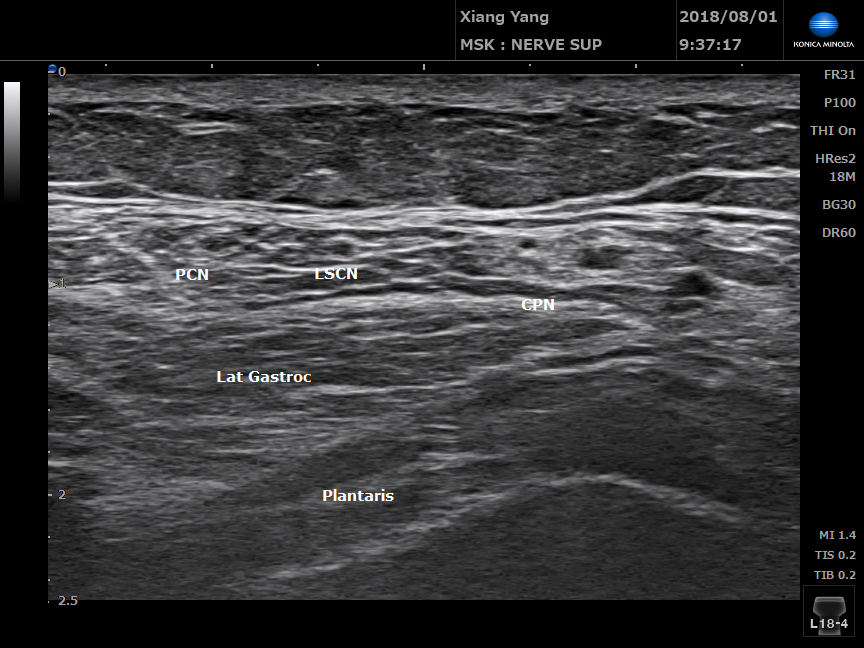

腓腸神經